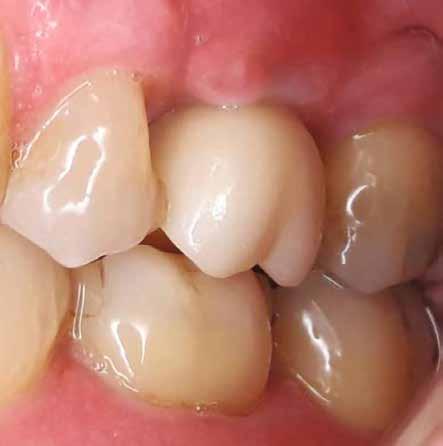

lási csavarokat (PEEK titáncsavarral) maximum 15 Ncm-rel húztuk meg (3–6. ábra). Az összes implantátum kiváló stabilitást mutatott (a mérésekhez Periotestet használtunk, a Medizintechnik Gulden jóvoltából), és teljesen osszeointegrálódott. Ezt a radiológiai vizsgálatok is megerősítették.

8. a–b. ábra: Végső röntgenfelvétel az implantátum helyzetéről (a) és a szájon belüli végső szituáció az 1. esetről (b).

Végső röntgenfelvétel az implantátum helyzetéről (a) és a szájon belüli végső szituáció a 2. esetről (b).

ábra: Végső röntgenfelvétel az implantátum helyzetéről (a) és a szájon belüli végső szituáció a 3. esetről (b és c).

tottuk (az okklúziós koncepciók alapján az implantációs pótlások nem voltak vezető fogak, és csak könnyű érintkezéseket alakítottunk ki, amelyeket artikulációs papírral ellenőriztünk). A páciensek instrukciókat kaptak a megfelelő szájhigiénére vonatkozóan, összpontosítva a fogköz kefékkel történő tisztítására. Végső kontroll röntgenfelvétel készült. A PEEK felépítmény nem radioopák, így az implantátum és a korona közötti távolság könnyen meghatározható a röntgenfelvételen: a felépítmény megfelelően illeszkedik az implantátumban, ha az implantátum válla és a korona alsó széle közötti rés 0,55 mm a röntgenfelvételen (8–11. ábra)

Minden páciens elégedett volt a kezelés eredményével, a funkcionális és az esztétikai eredmény egyaránt kielégítő volt. Az egyetlen megjegyzés – a teljes kezelés hosszú időtartama – a felső állkapocs esetében volt. A meghosszabbított, öt hónapos csontintegrációs periódus miatt, a teljes

eljárás több mint hat hónapig tartott. A kezelő szemszögéből a gyártó szigorú előírásainak betartása mellett nem volt jelentős különbség a titánimplantátumok használatához képest. A felső és alsó állcsont fogainak pótlásában a CERALOG implantátumok megfelelő és stabil alternatívának tűnnek a titánimplantátumokkal szemben.